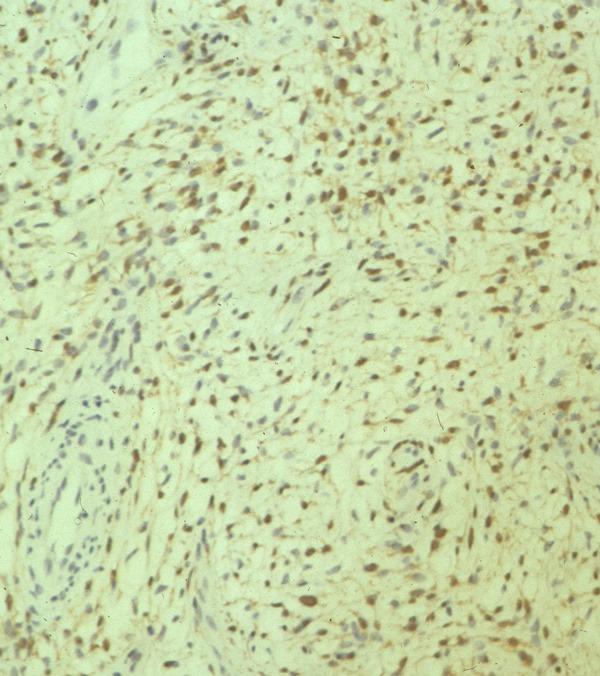

Microscopic Pathology

• Usually uninodular masses

• Surrounded by fibrous capsules consisting of epineurium and residual nerve fibers

• Distinct Pattern of alternating Antoni A and B areas

o Antoni A Area: Cellular area arranged in short bundles or interlacing fascicles

Spindle cells with wavy appearing nuclei. (Fig. 5 & 6)

o Antoni B Area: Less cellular and more myxoid (Fig. 7)

• Ancient schwannomas: a type of schwannoma that is typically larger and demonstrates cyst formation, calcification, hemorrhage, fibrosis. Ancient schwannomas can be mistaken for malignant peripheral nerve sheath tumors

• Mitotic activity is rare.

• S-100 positive staining; Vimentin positive

Fig. 5-7 Microscopic Pathology demonstrates 2 different patterns; Antoni A area with spindled hypercellular distribution with wavy appearing nuclei (Fig 5 & 6A) that palisades, known as Verocay Bodies (Fig 6B). Antoni B area is less cellular and more myxoid (Fig 7) than the Antoni A area. Mitotic activity is not visible.